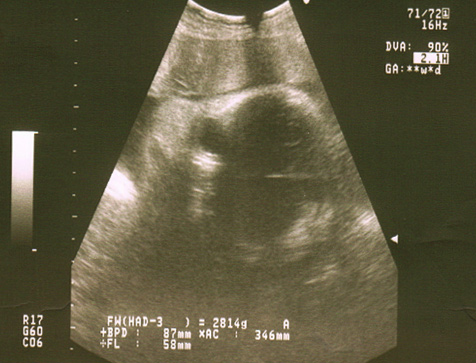

Ecografías de la semana 38 de embarazo

Ecografía semana 38: cara del feto. Si observamos la parte superior de la imagen, podemos identificar la cara del bebé de perfil con sus diferentes órganos: órbitas oculares, frente, nariz y boca.